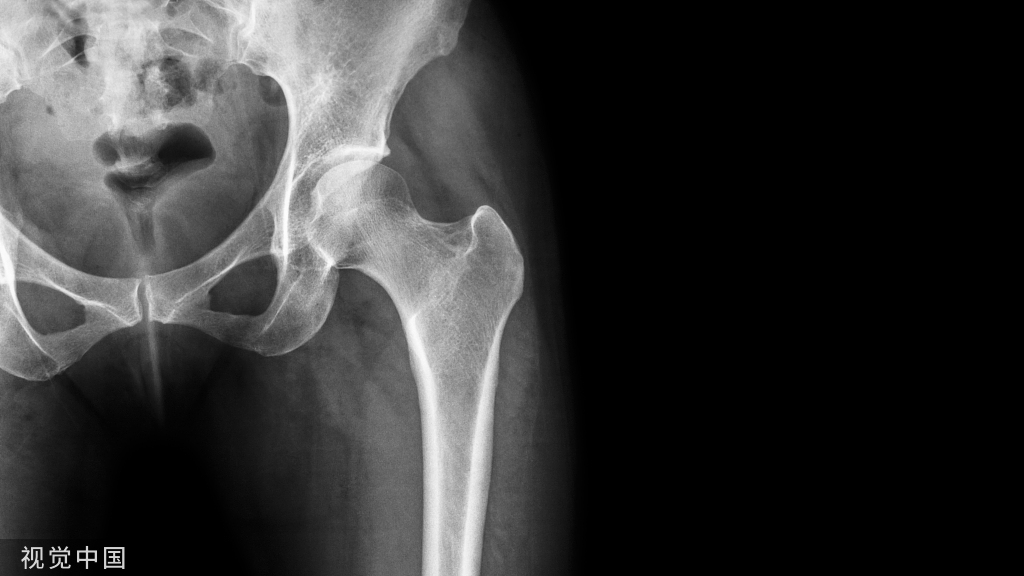

人工膝关节置换术(Knee replacement surgery)是骨科目前最常用且疗效确切的技术之一。TKA手术可以说是一个毫米级的手术,要想达到患者术后满意,精确的手术技巧是保证成功的必要条件。

膝关节的机械轴线和解剖轴线髋、膝关节内、外翻时会影响力线

标准的骨性对线股骨的解剖轴——应力轴=5~7°胫骨的解剖轴——应力轴=0 °

假体对线股骨远端切骨垂直于力学轴线胫骨切骨垂直于胫骨力学轴线